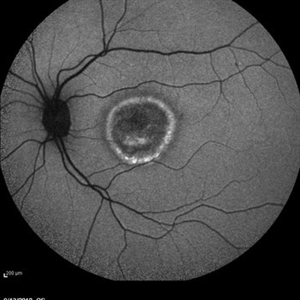

Best Disease Best DiseaseMar 9 2013 by Hamid Ahmadieh, MD Autofluorescence Imaging of the left eye of a 49-year-old man with decreased VA due to advanced Best disease. Photographer: Soodabeh Fooladin, Negah Eye Center, Tehran Imaging device: Heidelberg Spectralis Condition/keywords: autofluorescence imaging, Best disease

Best Disease Best DiseaseMar 9 2013 by Hamid Ahmadieh, MD Infrared imaging of the left eye of a 49-year-old man with decreased VA due to advanced Best disease. Photographer: Soodabeh Fooladin, Negah Eye Center, Tehran Imaging device: Heidelberg Spectralis Condition/keywords: Best disease, infrared image